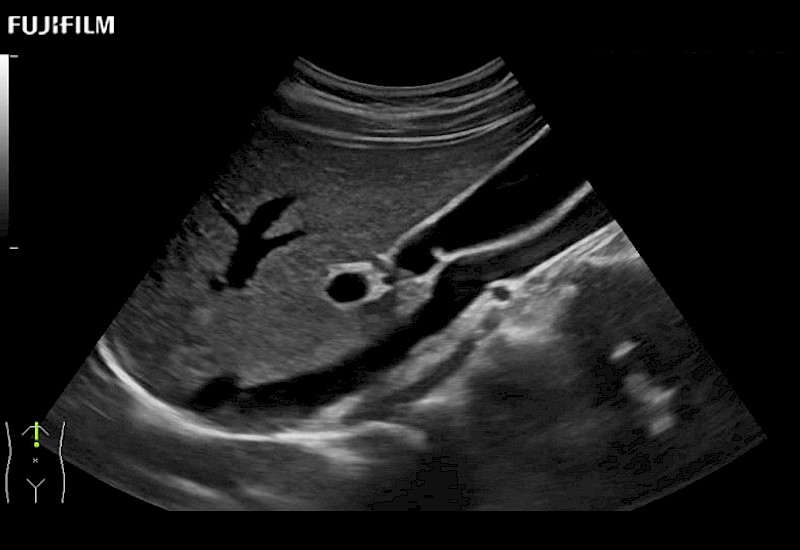

for use during general and laparoscopic procedures: Tumor localization & staging, Ablation, Resection, Biopsy, Transplant, Abdominal exploration, Robotic surgery

Curved array 4-way laparoscopic transducer for better visualization of targeted lesions.

Exclusive linear array 4-way laparoscopic transducer for better visualization of targeted lesions.

Exclusive linear array rigid laparoscopic transducer for better visualization of targeted lesions.